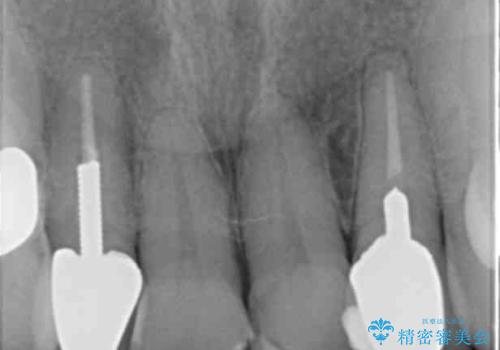

左上の前歯のみねじれが大きいため、歯の位置をひっこめたかぶせものにするために、神経の治療を行っています。

両側の歯の神経の治療および土台のやり替えは行っていません。